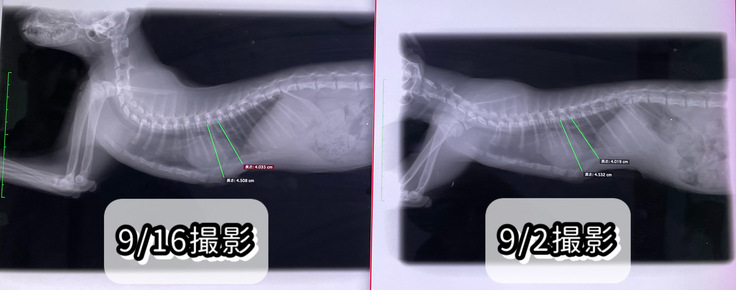

9/16(土)術後11回目の診察

本日は傷口の消毒とレントゲンを撮って

経過を診ていただきました。

傷口はかなり良くなって、次回の診察までにはほぼほぼ完治するだろう、とのことでした。

レントゲンも撮ってもらいましたが、

1〜2mmの戻りはありますが、

かなり良い感じ、とのことです!

体重も1.92kgになりました。